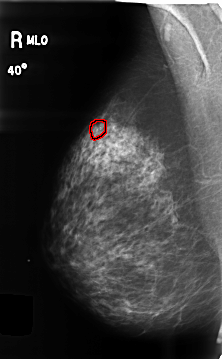

B_3459_1.RIGHT_MLO

RIGHT_MLO LINES 4656 PIXELS_PER_LINE 2880 BITS_PER_PIXEL 12 RESOLUTION 50 OVERLAY

FILE: B_3459_1.RIGHT_MLO.OVERLAY

TOTAL_ABNORMALITIES 1

ABNORMALITY 1

LESION_TYPE CALCIFICATION TYPE PLEOMORPHIC DISTRIBUTION CLUSTERED

ASSESSMENT 4

SUBTLETY 4

PATHOLOGY BENIGN

TOTAL_OUTLINES 1

BOUNDARY